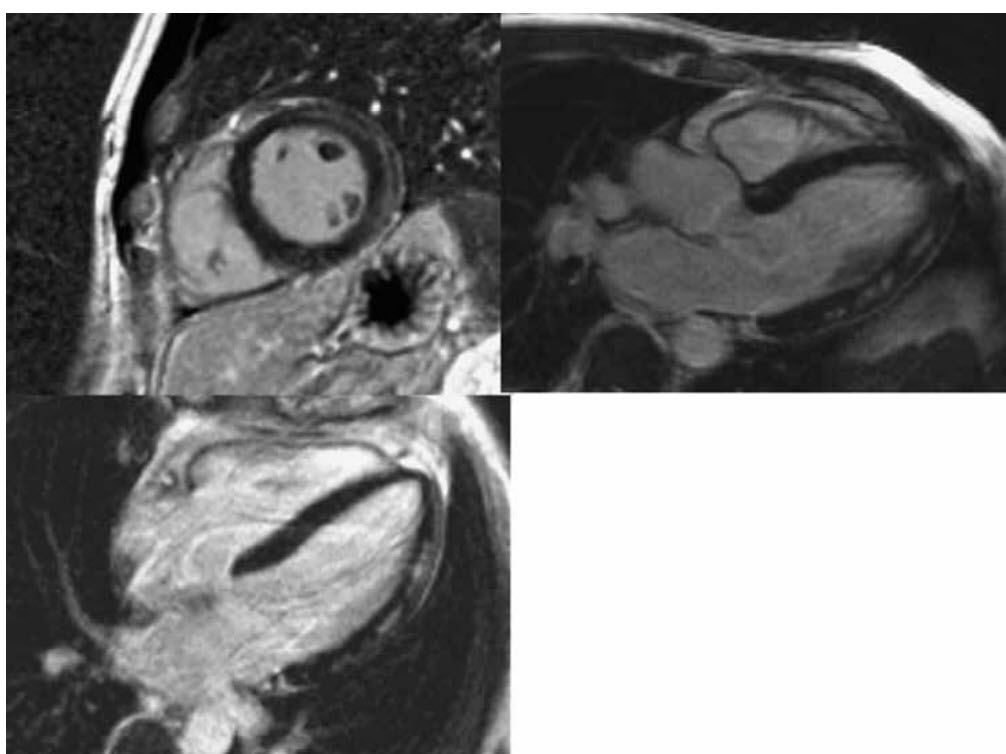

Video below shows the CMR long-axis cine images

Video below shows the short-axis cine images.

The late myocardial enhancement images are shown below

What is the diagnosis?

A. STEMI

B. Takotsubo

C. NSTEMI

D. Myocarditis

E. Hypertrophic cardiomyopathy